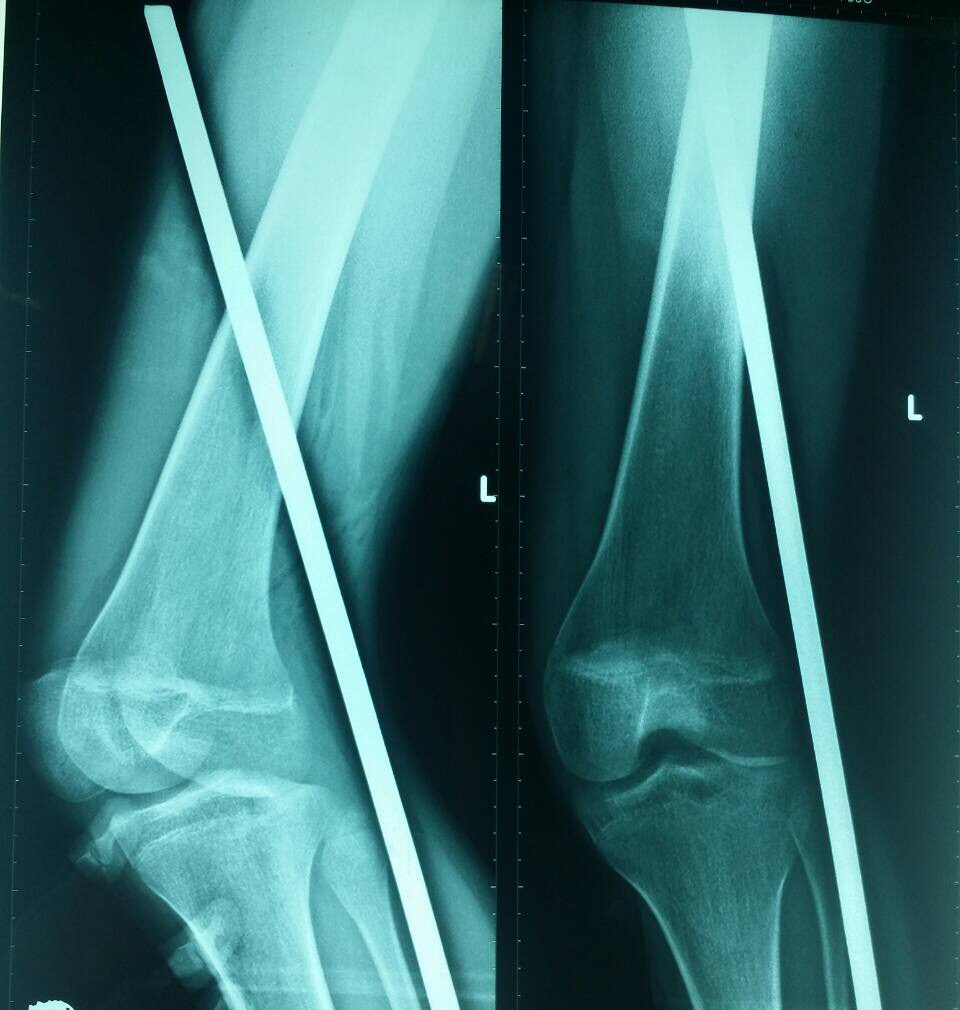

| Phim chụp X-quang đoạn sắt đâm xuyên thấu chân bệnh nhân. Ảnh: Bác sĩ cung cấp. |

Kết quả chụp X-quang cho thấy đoạn sắt đâm xuyên phần mềm không làm tổn thương dây thần kinh, mạch máu.